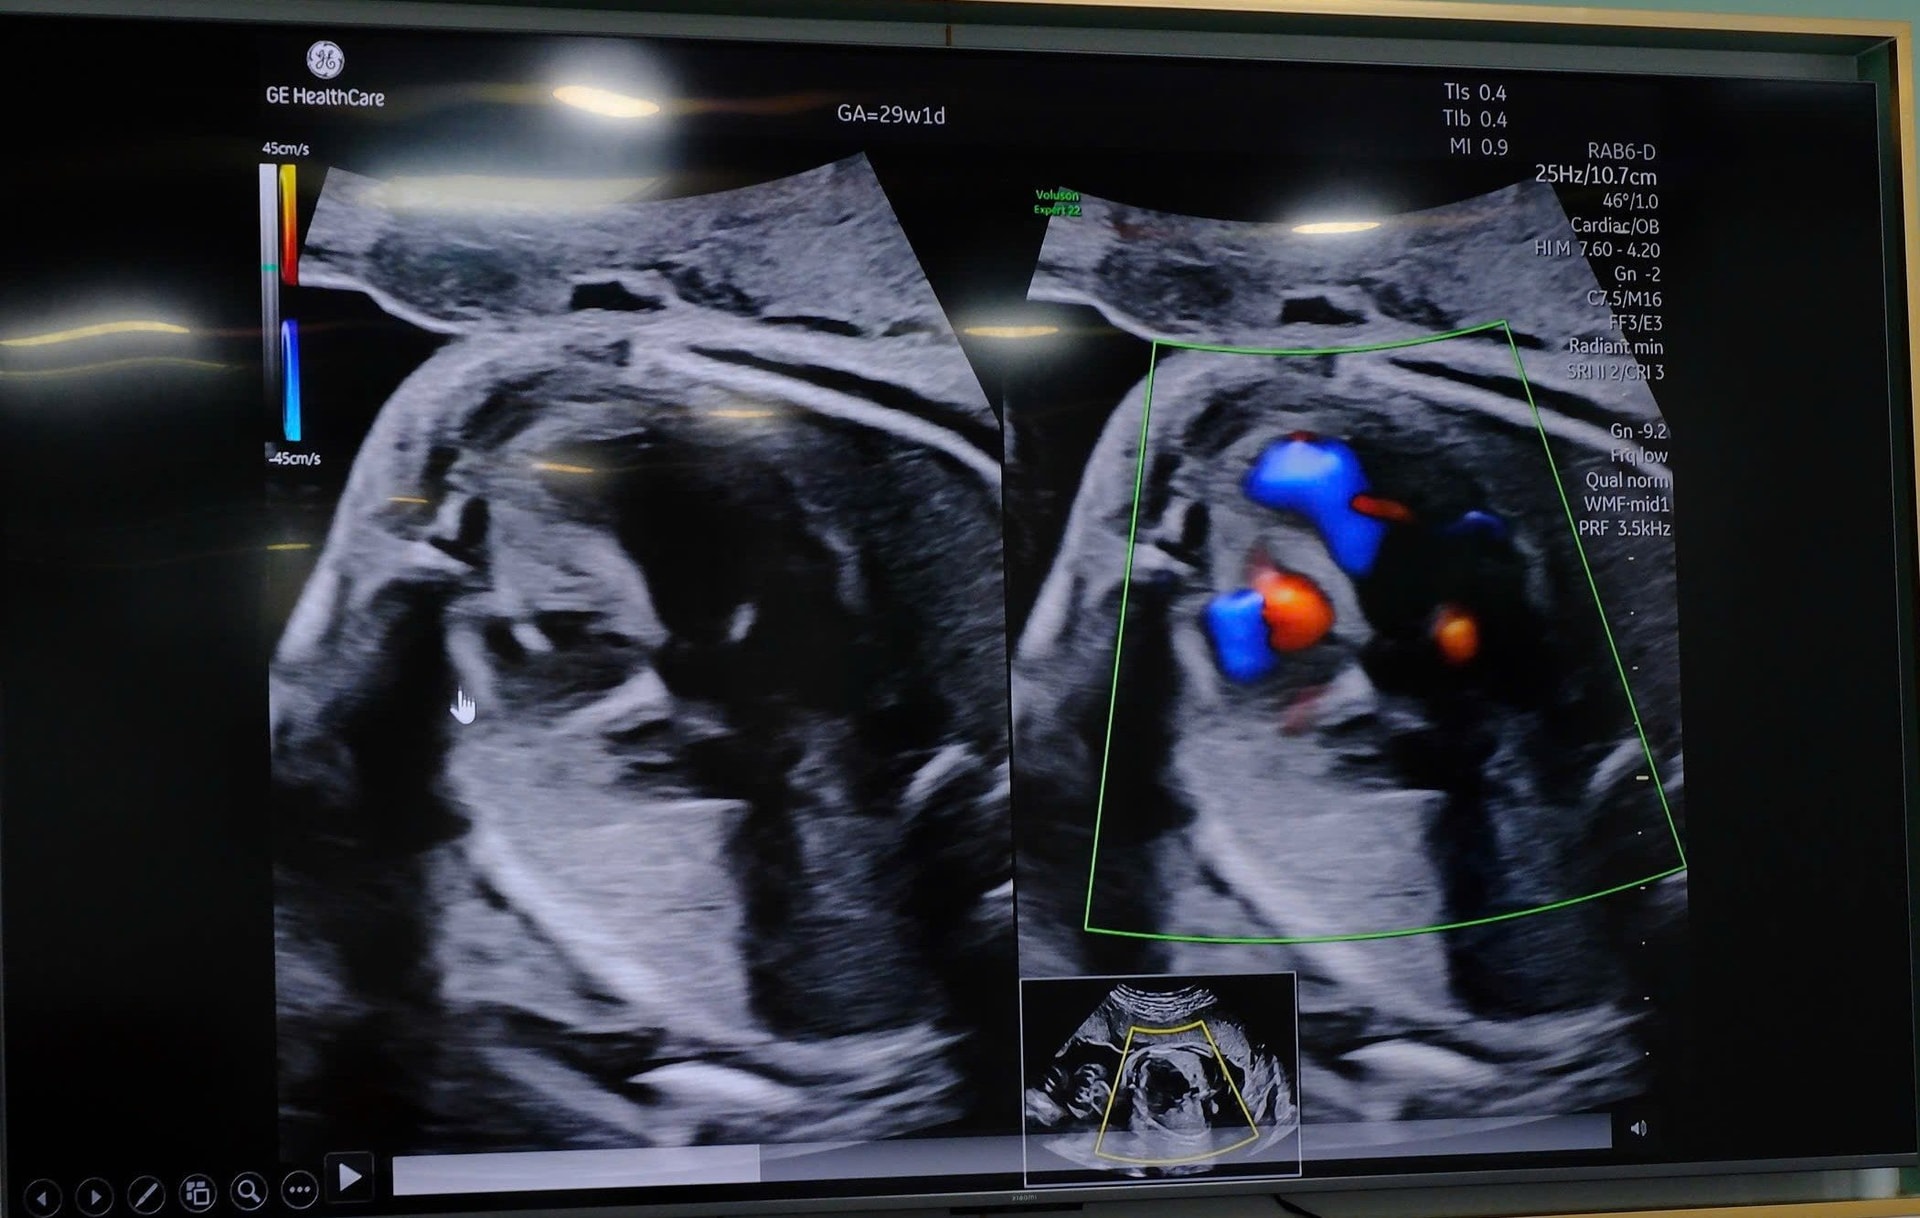

Tuy nhiên, đến tuần thai 22 - 24, qua siêu âm tim thai chuyên sâu, các bác sĩ ở một bệnh viện tư phát hiện thai bị bất thường tim bẩm sinh, chẩn đoán hẹp van động mạch phổi nặng kèm hở van ba lá. Nơi này đã chuyển chị đến theo dõi, hội chẩn chuyên sâu tại Bệnh viện Từ Dũ và Bệnh viện Nhi Đồng 1.

Trong quá trình theo dõi tiếp theo, bệnh lý tim thai có xu hướng tiến triển, với biểu hiện thiểu sản thất phải tăng dần cả về hình thái và chức năng, nguy cơ cao diễn tiến thành tim một thất nếu không can thiệp.

Trên cơ sở hội chẩn liên viện, đánh giá toàn diện về hình thái tim, chức năng thất phải và điều kiện can thiệp, các bác sĩ của hai bệnh viện đã thống nhất chỉ định can thiệp thông tim bào thai nhằm tạo cơ hội cho thất phải tiếp tục phát triển trong tử cung.

BS.CKII Trịnh Nhựt Thư Hương, Trưởng Khoa chăm sóc trước sinh tại bệnh viện Từ Dũ chia sẻ: Tại thời điểm tiến hành, thai nhi ở tư thế ngôi đầu, nghiêng trái, bánh nhau mặt trước làm gia tăng mức độ khó của thủ thuật. Đặc biệt, trong quá trình tiếp cận tim thai, cánh tay thai nhi vắt ngang trước ngực, che khuất đường vào buồng tim. Trước tình huống này, ê-kíp đã linh hoạt thực hiện một thủ thuật hỗ trợ nhỏ để di chuyển chi thai, tạo điều kiện thuận lợi cho việc tiếp cận vị trí can thiệp an toàn.

Sau khi tối ưu tư thế, quá trình xuyên kim qua thành bụng mẹ – tử cung – lồng ngực thai nhi và bơm bóng nong van động mạch phổi được thực hiện thuận lợi. Ca can thiệp thành công ngay lần xuyên kim đầu tiên, đảm bảo chính xác về kỹ thuật, hạn chế tối đa thời gian và nguy cơ cho cả mẹ và thai nhi.